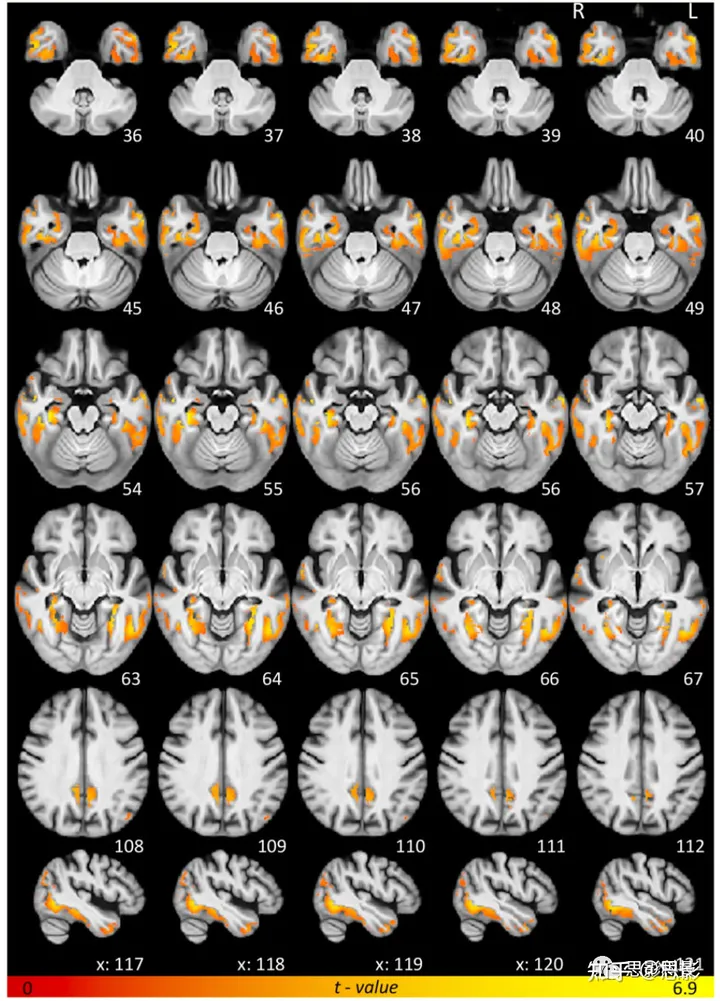

整个灰质QSM分析

体素级回归分析揭示,颞叶区域(颞部元感兴趣区域)的tau-PET摄取主要与包括双侧下和中颞回、梭状回、海马旁皮层和颞极在内的颞区广泛绝对磁敏感增加有关。此外,尽管较为稀疏,颞叶tau-PET示踪剂摄取也与顶叶区域(尤其是颞顶旁回)、前扣带皮层、后扣带皮层、侧向枕部和额叶区域如中额皮质和岛皮质的QSM协变(图1和补充表1)。反向对比,即绝对QSM和tau-PET值之间的负相关,在整个大脑中都不显著。

图1 整个灰质QSM体素级回归结果

簇显示了正向体素级关联的显著结果的t值(P ≤ 0.01 FWE):绝对QSM 与 tau-SUVR + 年龄的关系。结果按照放射学惯例显示。为了便于可视化,结果已经被映射到MNI 152空间(蒙特利尔神经学院模板),使用ANTs程序,并在整个研究的解剖模板上展示。